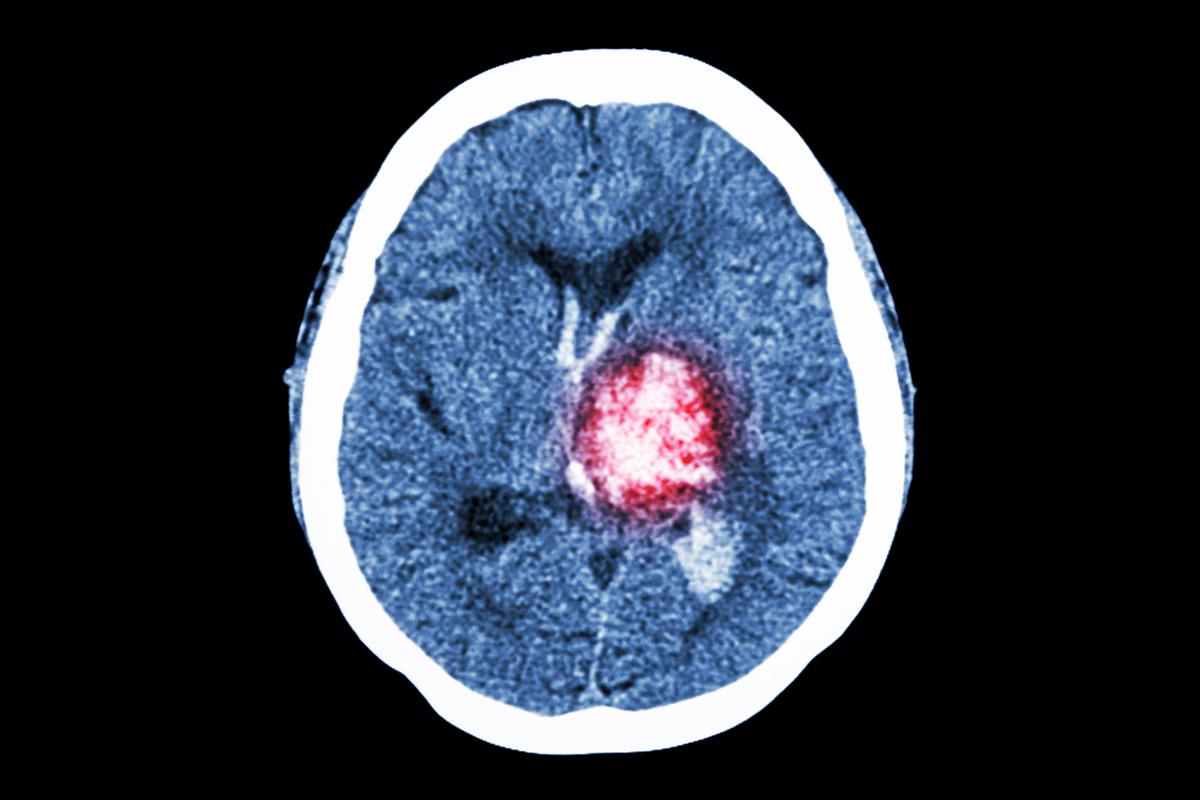

Med bedre behandling vil flere kunne overleve hjerneblødning

Hjerneblødning tar livet av like mange i dag som på 1990-tallet. Det trenger ikke være slik. Med bedre behandling kan de som får hjerneblødning leve lenger.

- Hjerneblødning er én av tre typer hjerneslag, der en sprekk i blodkaret fører til at blodtilførselen til deler av hjernen blir skadet. Det er den farligste formen for hjerneslag og rammer 10–15 prosent av de som får slag. Den vanligste typen er hjerneinfarkt med blodpropp (80–85 prosent), og den minst utbredte er hjernehinneblødning der en utposning på et blodkar sprekker (5 prosent).